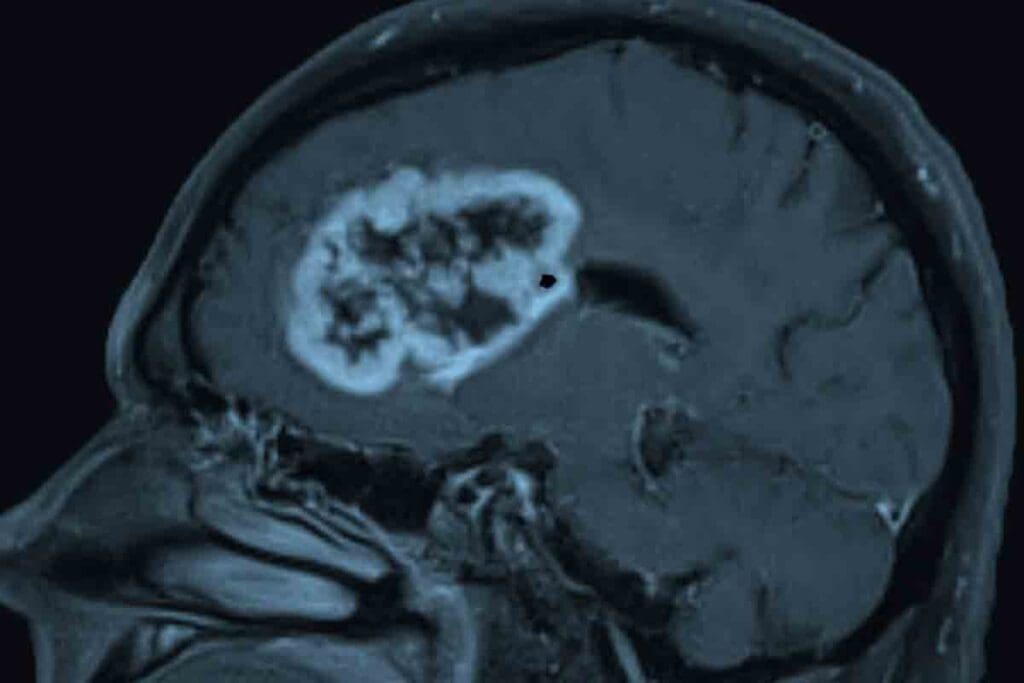

Imaging Studies (MRI, CT Scans)

Imaging is vital for diagnosing pediatric GBM. MRI and CT scans help us see the tumor in the brain. MRI gives us clear images of soft tissues, showing the tumor’s size and where it is.

Common Locations in the Brain

GBM can pop up anywhere in the brain but often shows up in the cerebral hemispheres. It likes the frontal lobe and areas above the tentorium. It can also appear in the brainstem and cerebellum, but that’s less common in kids.